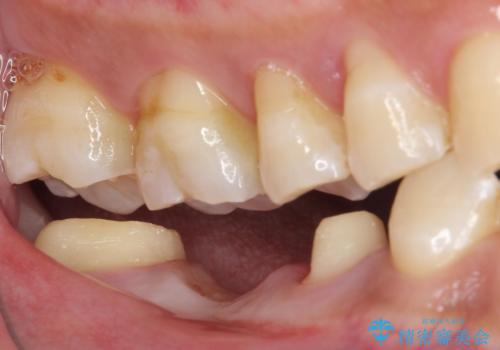

- 以前他院にて、保険診療で治療した金属のブリッジをやり替え希望の患者様です。

奥歯であっても、大きく笑うと金属色が目立ちます。

金属ブリッジを除去し、虫歯を完全に除去し、形を整え、

精度の高いシリコーン材料にて型どりをしました。